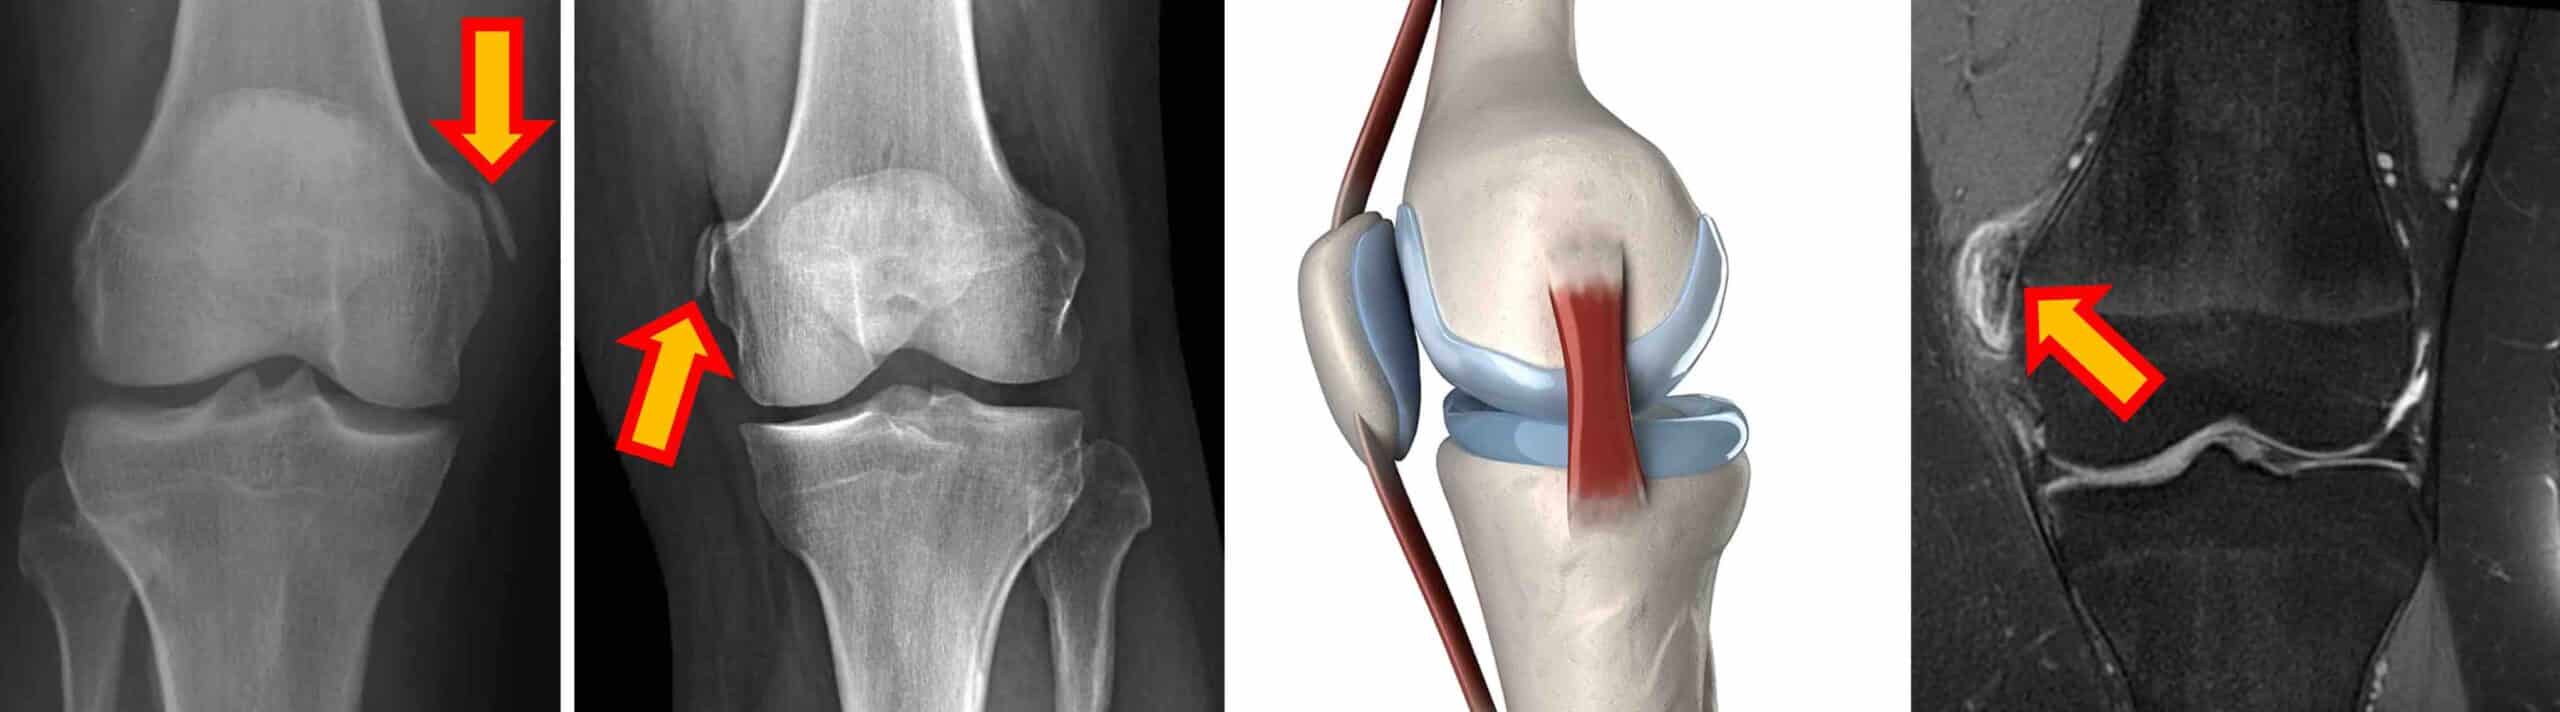

DIAGNÓSTICO

A lesão de Pellegrini-Stieda é diagnosticada através do exame físico do joelho sintomático e confirmado por exames de imagem. Uma calcificação característica é observada na região da origem do ligamento colateral medial no côndilo medial do joelho no RX e na ressonância magnética.